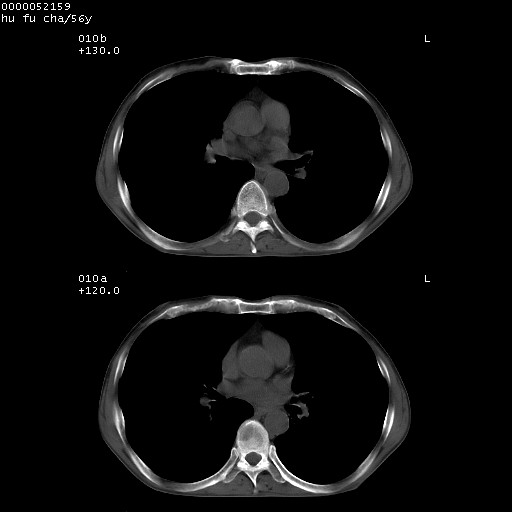

以下是引用zsl6918在2008-8-25 22:47:00的发言:[br]胸骨,胸椎及肋骨均可见多发转移表现,肝内低密度结节不除外转移。原发灶可能在右肺。双侧可见支扩表现。

以下是引用宇宙ct在2008-8-25 23:26:00的发言:[br][br] 胸骨,胸椎及肋骨均可见多发转移表现,肝内低密度结节不除外转移。原发灶可能在右肺。双侧可见支扩表现。 [br] [br]

以下是引用卜一在2008-8-26 8:02:00的发言:[br][br] 支持:肺癌并肺内,胸骨,胁骨,胸椎及肝内转移!另:左肺支气管扩张征伴感染! [br]

以下是引用zjzjr在2008-8-26 11:03:00的发言:[br]支持:肺癌并肺内,胸骨,胁骨,胸椎及肝内转移!另:左肺支气管扩张征伴感染!